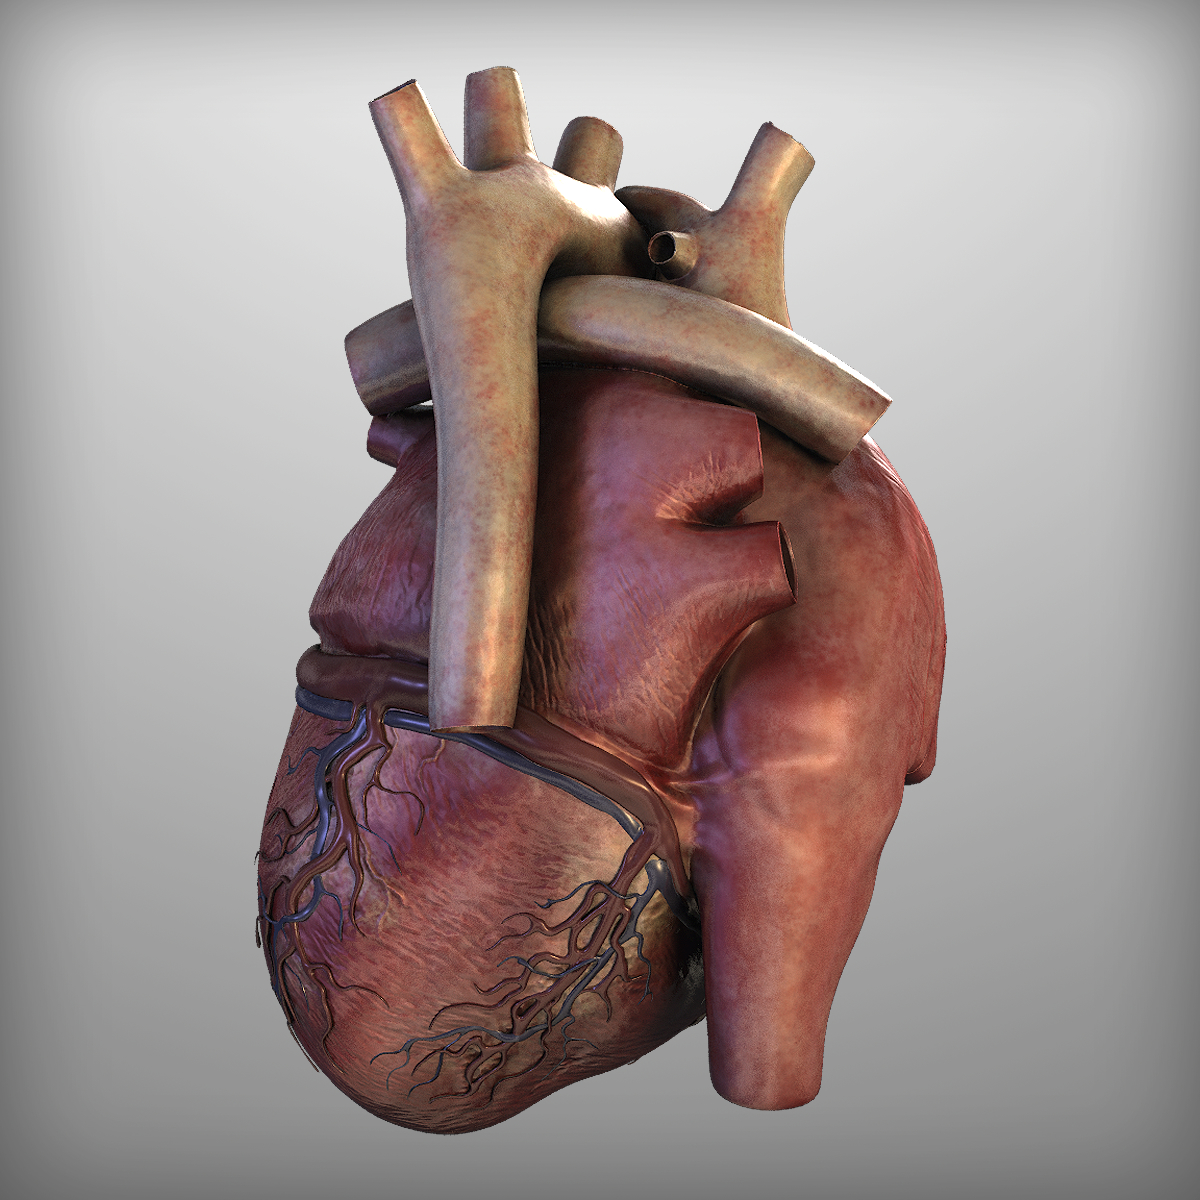

Human Heart Drawing Outline at GetDrawings | Free download  3d anatomy human heart

3d human heart  Animated Realistic Human Heart - Medically 3D asset

3D human heart anatomy model - TurboSquid 1283134  anatomy human heart 3d c4d

anatomy human heart 3d c4d  Modeled human heart section 3D model - TurboSquid 1657004